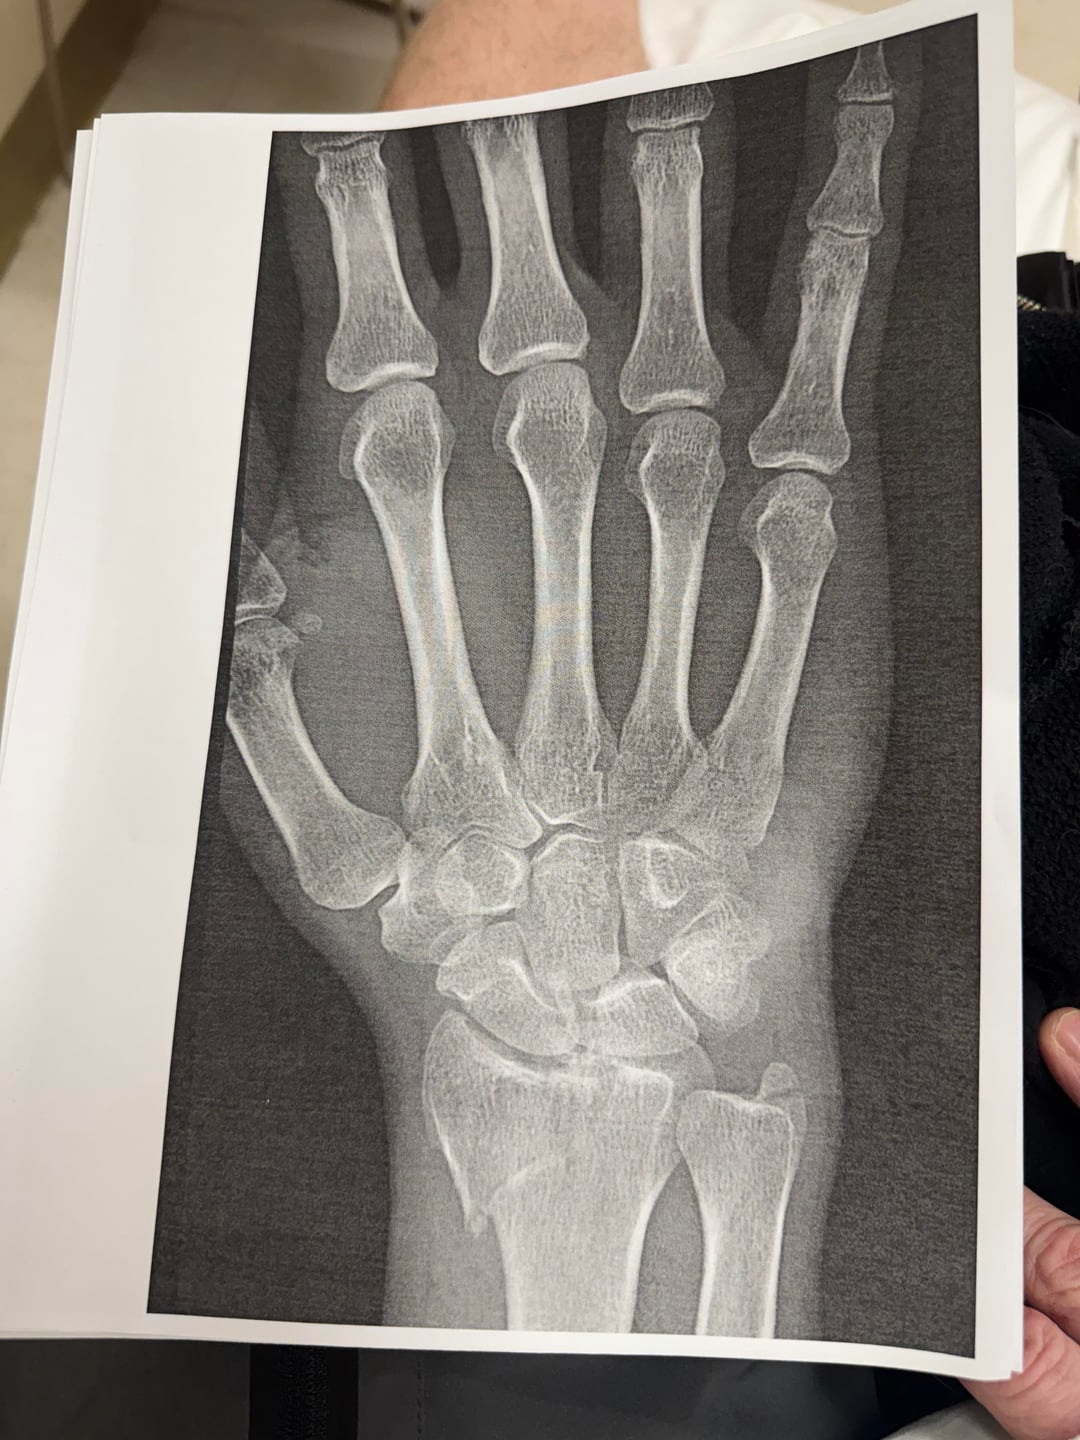

I went out to my local trail last night and tried to squeeze a ride in before it got too dark. It was going really well but I took a tricky corner over some roots too fast and ended up eating it. Now I’m waiting until tomorrow to call the hand specialist at my orthopedist since this will likely require surgery to repair.

Sorry man. Hopefully to put your mind at ease a bit: I had a worse break (I think) last year – head of radius in 6 pieces and totally misaligned; looks like you have one clean break. Will require surgery to put a plate in. I was back on the bike 4 months after the accident with surgeon permission.